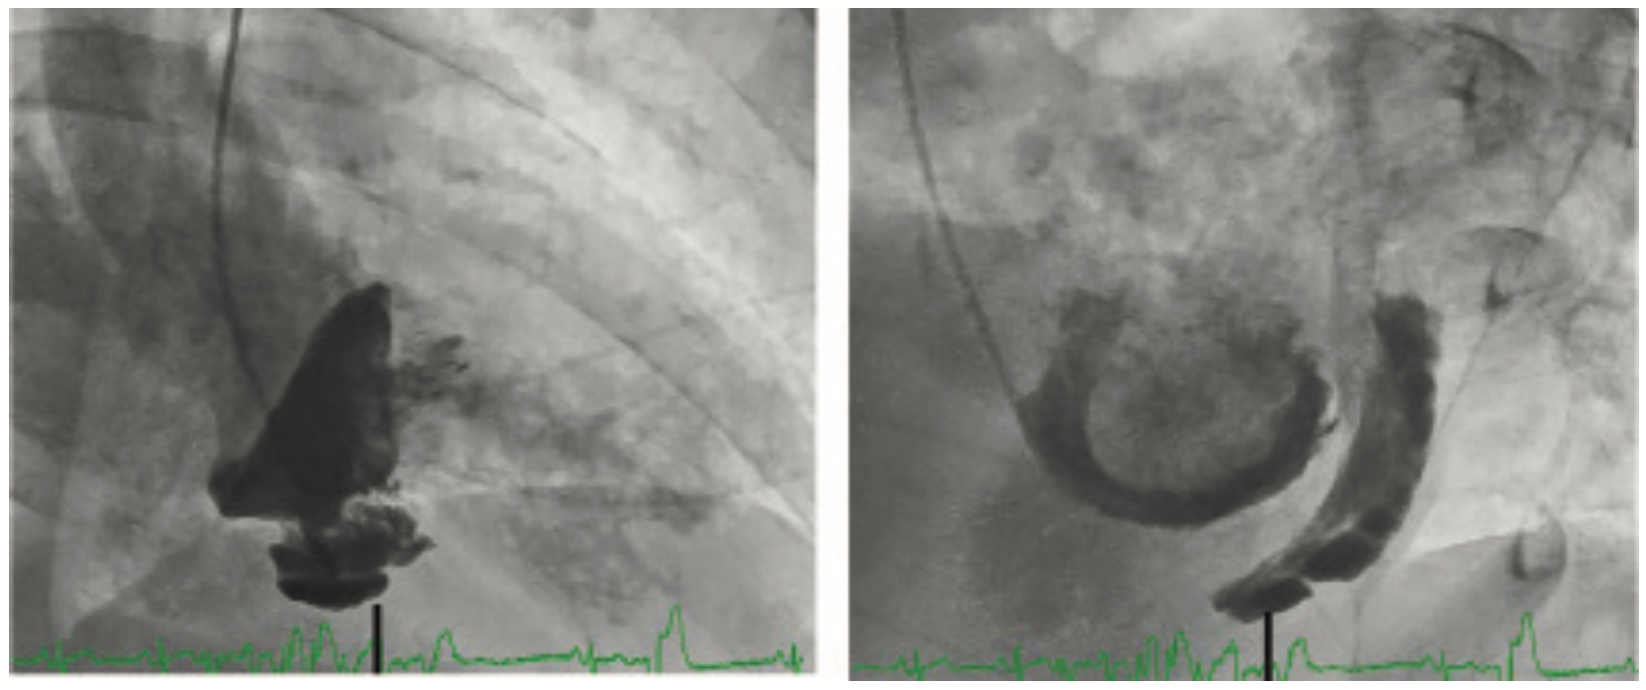

Hypotension After Ventriculography

Rarely, hypotension after ventriculography may occur due a contrast reaction, arrhythmia (ventricular tachycardia [VT]/ventricular fibrillation [VF]) or left ventricular (LV) perforation. We have previously discussed the dangers of end-hole catheter ventriculography1 by showing a patient with extensive myocardial contrast staining following LV injection using a universal radial Jacky catheter (Terumo) (Figure 3).